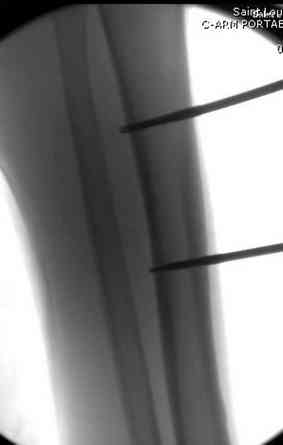

здесь случай с политравмой, перелом зафиксирован  наружным

фиксатором, после третьей irrigation&debridment фиксация бедра

пластиной с последующей кожной пластикой.

Вложение не в текстовом формате было извлечено…

Имя     : 4 tibia exfix 2 a.jpg

Тип     : image/jpeg

Размер  : 15056 байтов

Описание: отсутствует

Url     : http://weborto.net:8080/pipermail/ortho/attachments/20080516/ebe5bb74/attachment-0014.jpg